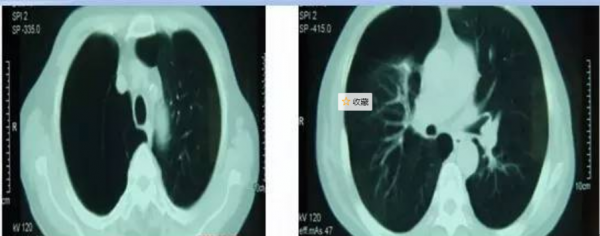

胸部CT顯示右側氣胸,雙肺肺氣腫

在全麻胸腔鏡下右肺大皰切除+肺減容術。手術順利,在胸腔鏡下用切割縫合器加墊片呈倒U型切除右上肺周邊20%氣腫肺組織及肺大皰。